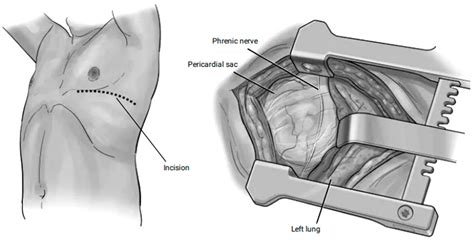

• Subxiphoid Approach: This is often the preferred method, performed through a small incision just below the sternum (breastbone). It is generally less invasive and can be performed under local or general anesthesia.

• Thoracoscopic Approach (VATS): Video-Assisted Thoracoscopic Surgery uses small incisions in the chest wall with the aid of a camera. This allows for a better visualization of the pericardium and is beneficial if there are underlying lung or pleural issues.

During the operation, the surgeon carefully makes the chosen incision. Once the pericardial sac is reached, they create the "window" by removing a small section of the membrane. This creates a permanent drainage channel. The surgeon will then inspect the area for any signs of infection or tumor growth, often taking a tissue biopsy if a malignancy is suspected. Once the fluid is drained and the opening is secured, a drainage tube may be left in place for a day or two to monitor for any remaining fluid buildup before the incisions are closed with sutures or surgical staples.

• Injury to adjacent structures, such as the phrenic nerve or lungs.